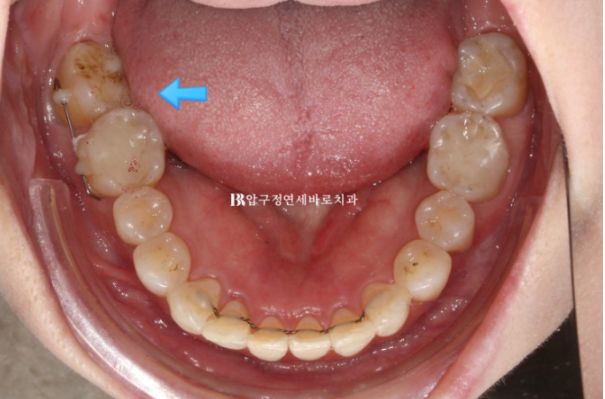

확실한 가위교합 개선을 위해 입천장에 미니스크류를 심었습니다.

24.07

마찬가지로 쓰러진 맨 뒤 큰어금니를 확실하게 세우기 위해 미니스크류를 심었습니다.

미니스크류는 총 2개 심고

미지한 부분들을 더 고치기 위해서 추가장치 재제작에 들어갔고 24년 8월부터 24년 12월까지 4달간 두번째 세트 14개 장치를 더 낀 후 모습입니다.

24.12

두번째 세트를 진행하는 도중에 쓰러진 큰 어금니를 좀 더 강한 힘으로 세우고자 부분적으로 MTA 장치를 붙이고 철사를 넣었습니다.

앞니 배열 개선과 가위교합 개선

쓰러진 큰 어금니는 잘 세웠습니다.